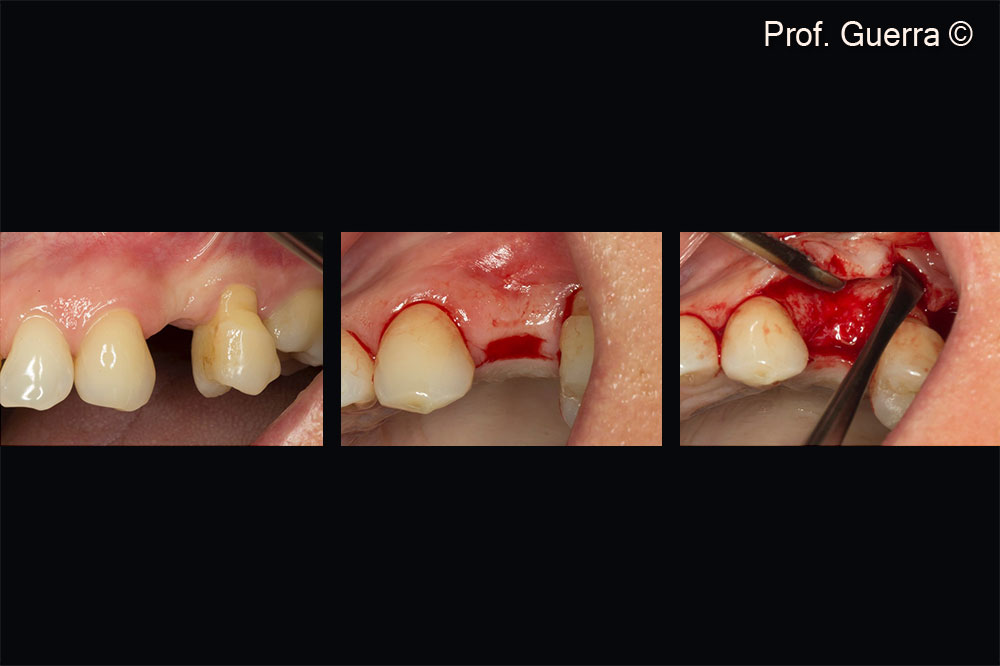

At the time of the implant placement, a male patient (45 years old) shows a dental dehiscence.

Left) missing first upper left premolar (24); Middle) envelop incision; Right) full flap thickness